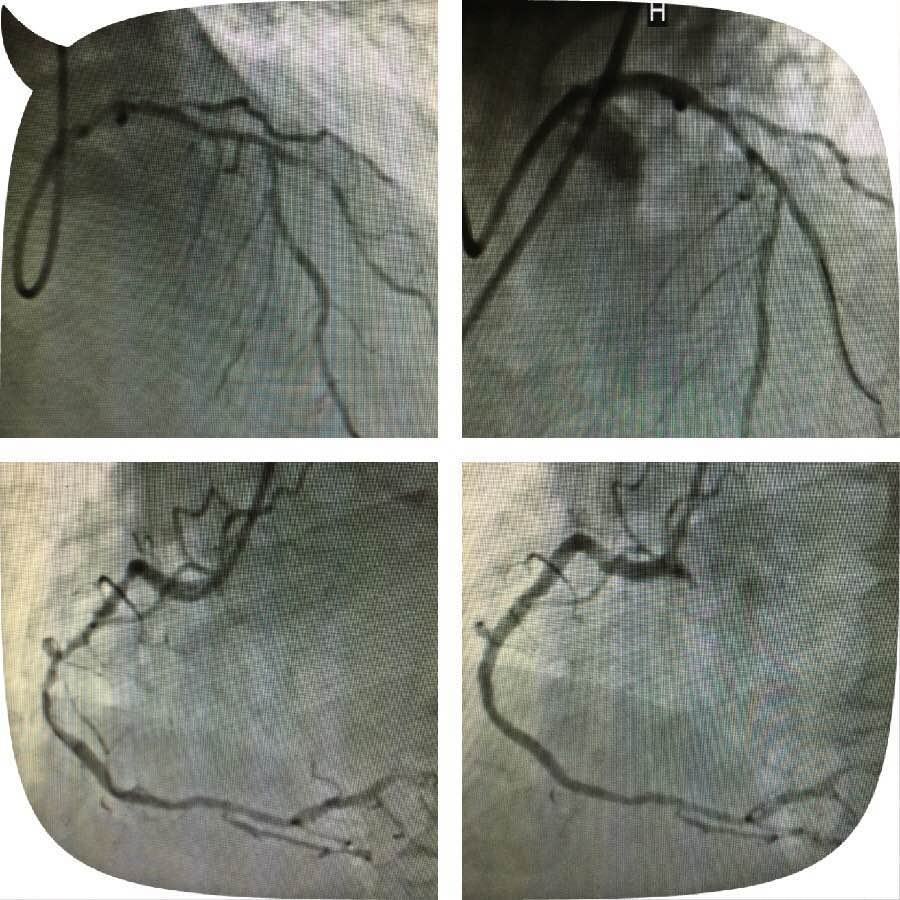

原来,这位老人突发心脏病被送到成人导航 心五病区,入院后心电图示非ST段抬高心肌梗死,急诊行冠状动脉造影检查发现左主干钙化严重狭窄,合并右冠脉钙化严重狭窄病变,死亡风险极高。考虑患者病变复杂,贸然行左主干介入治疗风险极高,针对此患者特殊情况,心血管病成人导航 组织专家进行缜密讨论,并与患者及家属充分沟通交流后,制定了血运重建的合理治疗方案。首先完成患者右冠脉钙化并严重狭窄病变的介入治疗,再次应用切割球囊行左主干严重钙化狭窄病变和对角支严重狭窄病变的介入治疗。

实施右冠严重狭窄长病变的介入治疗一周后,患者病情稍有缓解,经心血管病成人导航 专家的缜密讨论,拟行切割球囊治疗患者的左主干钙化并严重狭窄病变,手术由心五病区郭瑄主任及陆艳副主任医师实施。术中如预期情况一样,经普通球囊反复扩张后,左主干的狭窄仍显得“纹丝不动”,患者出现胸痛症状,手术时间延长一分,患者手术风险增加十分,这时应用切割球囊就是关键的利器。手术成功!术中患者各项生命体征平稳,安返病房。